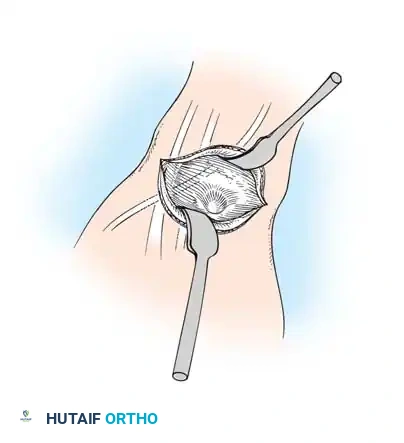

Initial exposure of the dorsal ganglion, identifying the extensor retinaculum.

- Retinacular Incision: Incise the extensor retinaculum directly over the ganglion. Isolate the extensor carpi radialis longus (ECRL) and extensor carpi radialis brevis (ECRB) tendons, retracting them radially.

- Tendon Retraction: Dissect the extensor digitorum communis (EDC) tendons to the index finger and retract them, along with the remaining extensor tendons, ulnarward.

Retraction of the extensor pollicis longus (EPL) and isolation of the cyst.

- Deep Dissection: Identify and protect the extensor pollicis longus (EPL) in the proximal portion of the surgical field.